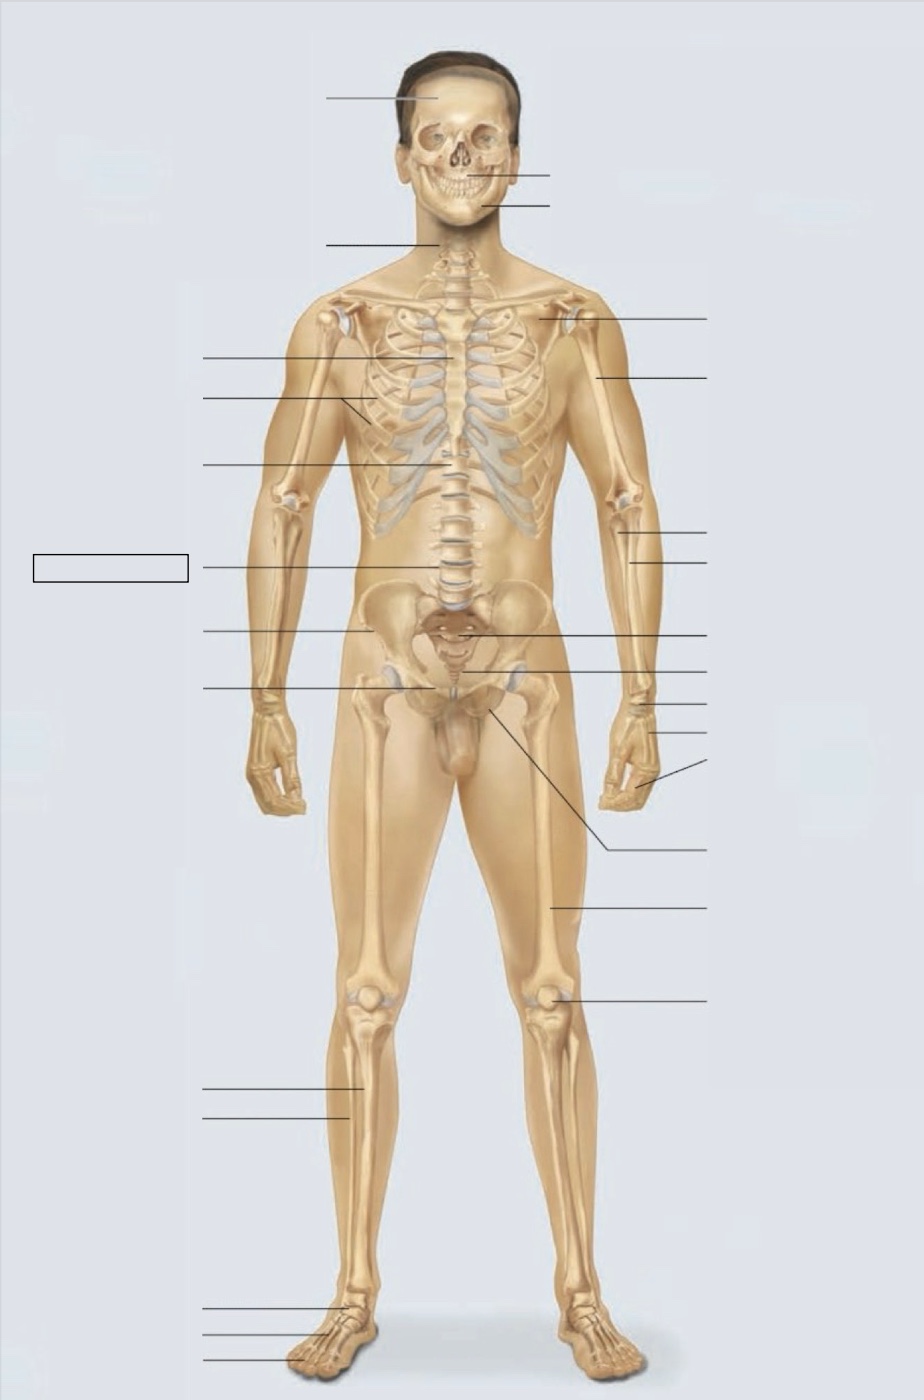

maxilla

mandible

scapula

humerus

ulna

radius

sacrum

coccyx

carpals

metacarpals

phalanges

ischium

femur

patella

phalanges

metatarsals

tarsals

fibula

tibia

pubis

ilium

lumbar vertebrae (L4)

thoracic vertebrae (T11)

ribs

sternum

cervical vertebrae

skull